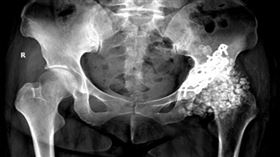

痛到難行!體內取出259顆軟骨瘤 醫驚呆

大陸福建省福州市一名40歲王小姐,由於大腿與臀部不時...